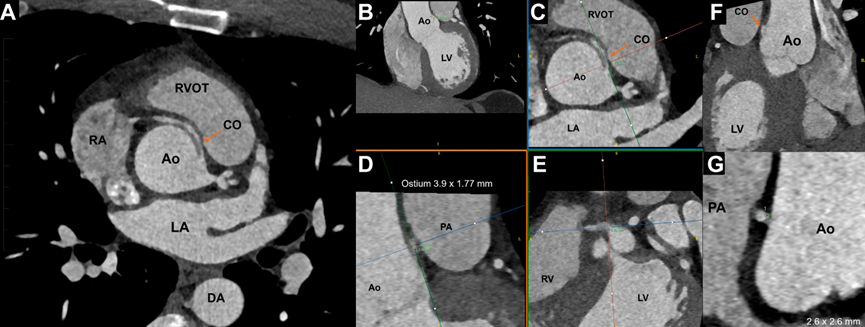

患者症状与负荷超声检查缺乏缺血客观证据之间存在矛盾,因此进一步行冠状动脉CT

图2

此外,该异常RCA发出了供应窦房结的动脉分支(图3)。